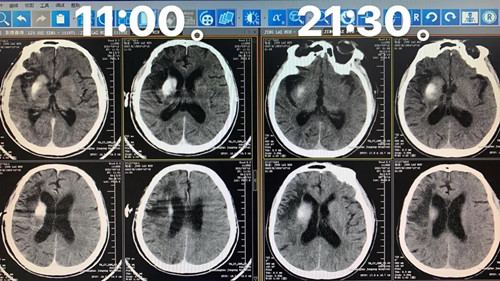

术后即刻及术后10小时头CT显示右尾状核头核心梗死灶形成伴随造影剂滞留,无大面积脑梗死及颅内出血发生。